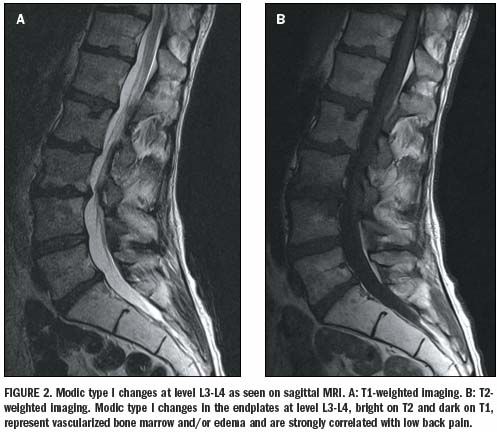

Изменение по типу modic 1

Изменение по типу modic 1 110 фотографий